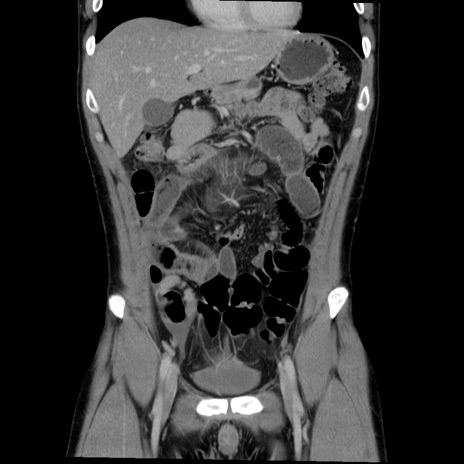

症例36(冠状断像)

【症例】20歳代 男性

【主訴】心窩部痛

【現病歴】今朝より上腹部痛あり。一旦軽快していたが再度出現したため救急要請。昨日夕に白身の魚を含む刺身を食べた。

【身体所見】BP 136/89mmHg、HR 74/min、BT 37.0℃、腹部:膨満、軟、心窩部に圧痛あり。反跳痛なし、筋性防御なし、腸雑音やや亢進あり。

【データ】WBC 17700、CRP 0.48